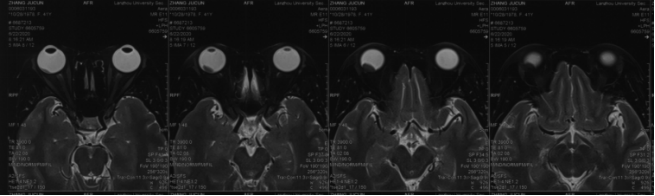

• Orbital MRI (Right Eye):A mound-shaped abnormal signal with mild enhancement was observed on the posterior upper and lower walls of the right eyeball, suggestive of melanoma.

• Target Delineation: MRI images were fused with CT scans for precise delineation of the choroidal and lung lesions.

Figure 4: Abnormal mound-shaped signal on the posterior upper and lower walls of the right eyeball, showing mild enhancement. Melanoma cannot be ruled out. A nodule is observed on the posterolateral wall of the right eyeball, exhibiting short T1 and T2 signals, with high signal on DWI